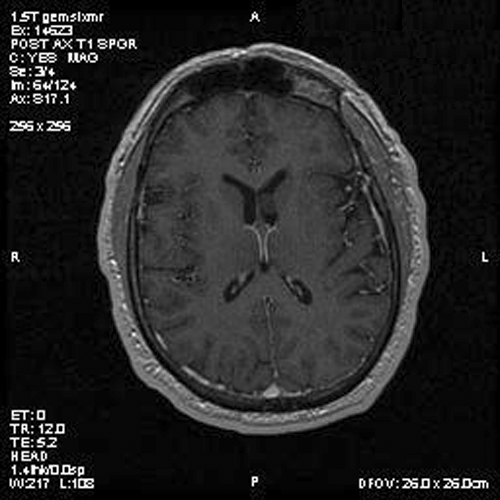

Panel A is T1-weighted post contrast MR image, Panel B is a SPGR T1-weighted post contrast MR image and Panel C is FSE T2-weighted image. Panel D and E are taken from cytologic preparation from intraoperative consultation. Panel F to H are taken from frozen sections. Panel I to L are taken from paraffin section.

Image of the case: In the left frontal horn there is a well demarcated, subependymal mass measuring approximately 1.1 x 0.5 cm which is relatively hyperintense to white matter on T1-weighted image (Panel A and B) as well as T2-weighted image (Panel C) sequences. It does not enhance on the post contrast images. There is no obstruction of the foramen of Monro.